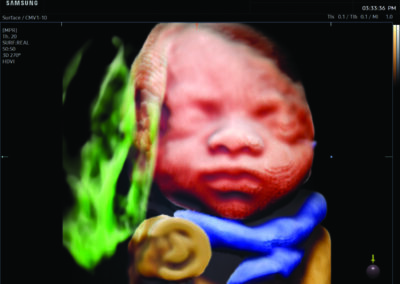

Comprehensive, advanced and expert MFM care for high-risk pregnancies

- Fetal anomalies